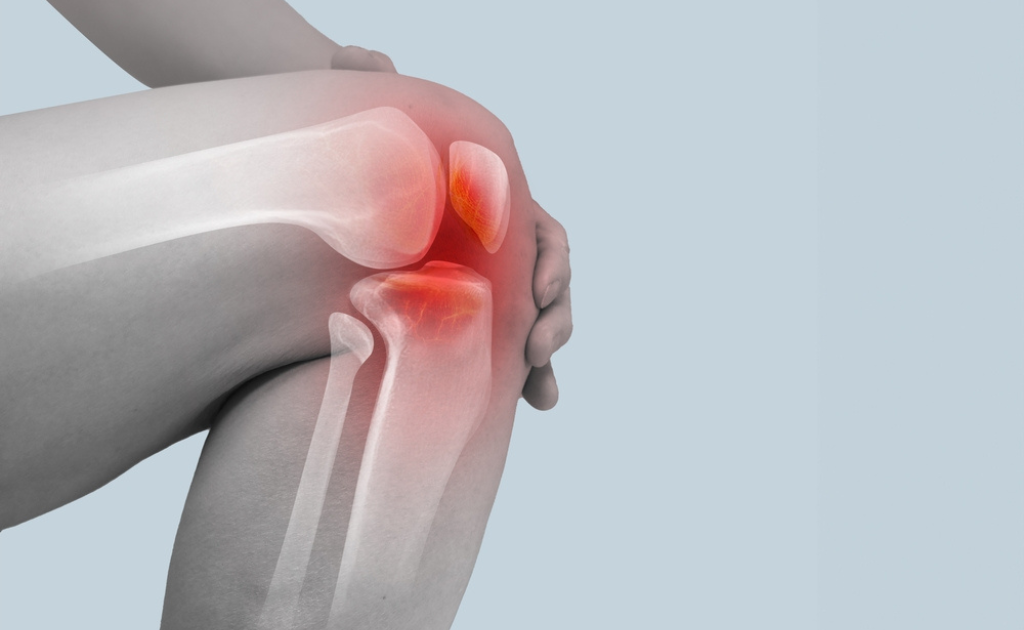

হাঁটু ব্যথা থেকে পরিত্রাণের কিছু কার্যকর উপায়

0 SHARES Share Tweet শায়লা জামান ছোটবেলা থেকেই নামাজের প্রতি খুব যত্নশীল। পাঁচ ওয়াক্ত নামাজের একটাও বাদ দেন না। কিন্তু ক...